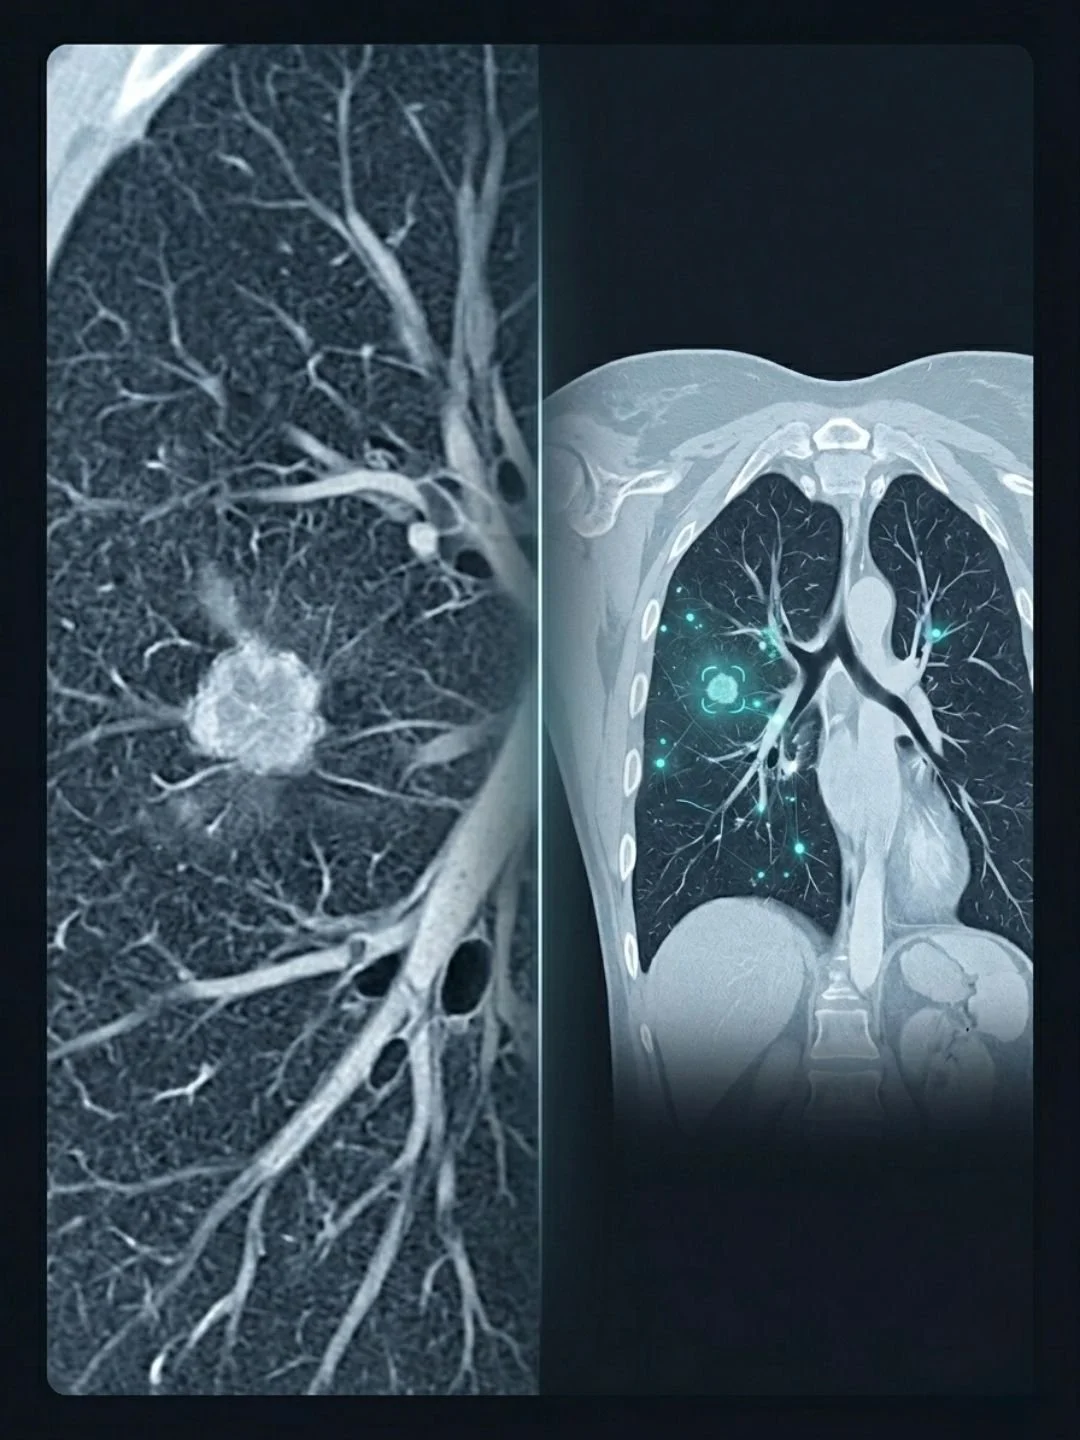

The team's solution is a model they call C-Swin. It combines two different types of neural network architecture working together. A convolutional neural network handles the fine-grained local features, the kind of detailed pattern recognition that picks up small lesions and subtle textures. A Swin Transformer, an architecture that uses a shifting window approach to analyse spatial regions of the image, handles the broader context. The two components work in parallel, their outputs integrated rather than sequential.

Researcher Inzamam Mashood Nasir, based at KTU, describes it simply. One part of the model focuses on small details, such as tiny spots or textures in the lungs, while another looks at the overall image and understands the bigger picture. You can think of it as having a magnifying glass and a full view of the scan at the same time.

Distinguishing between benign (non-cancerous) nodules and malignant tumours is one of the hardest tasks in radiology; getting it wrong leads to either missed cancers or unnecessary, invasive biopsies.